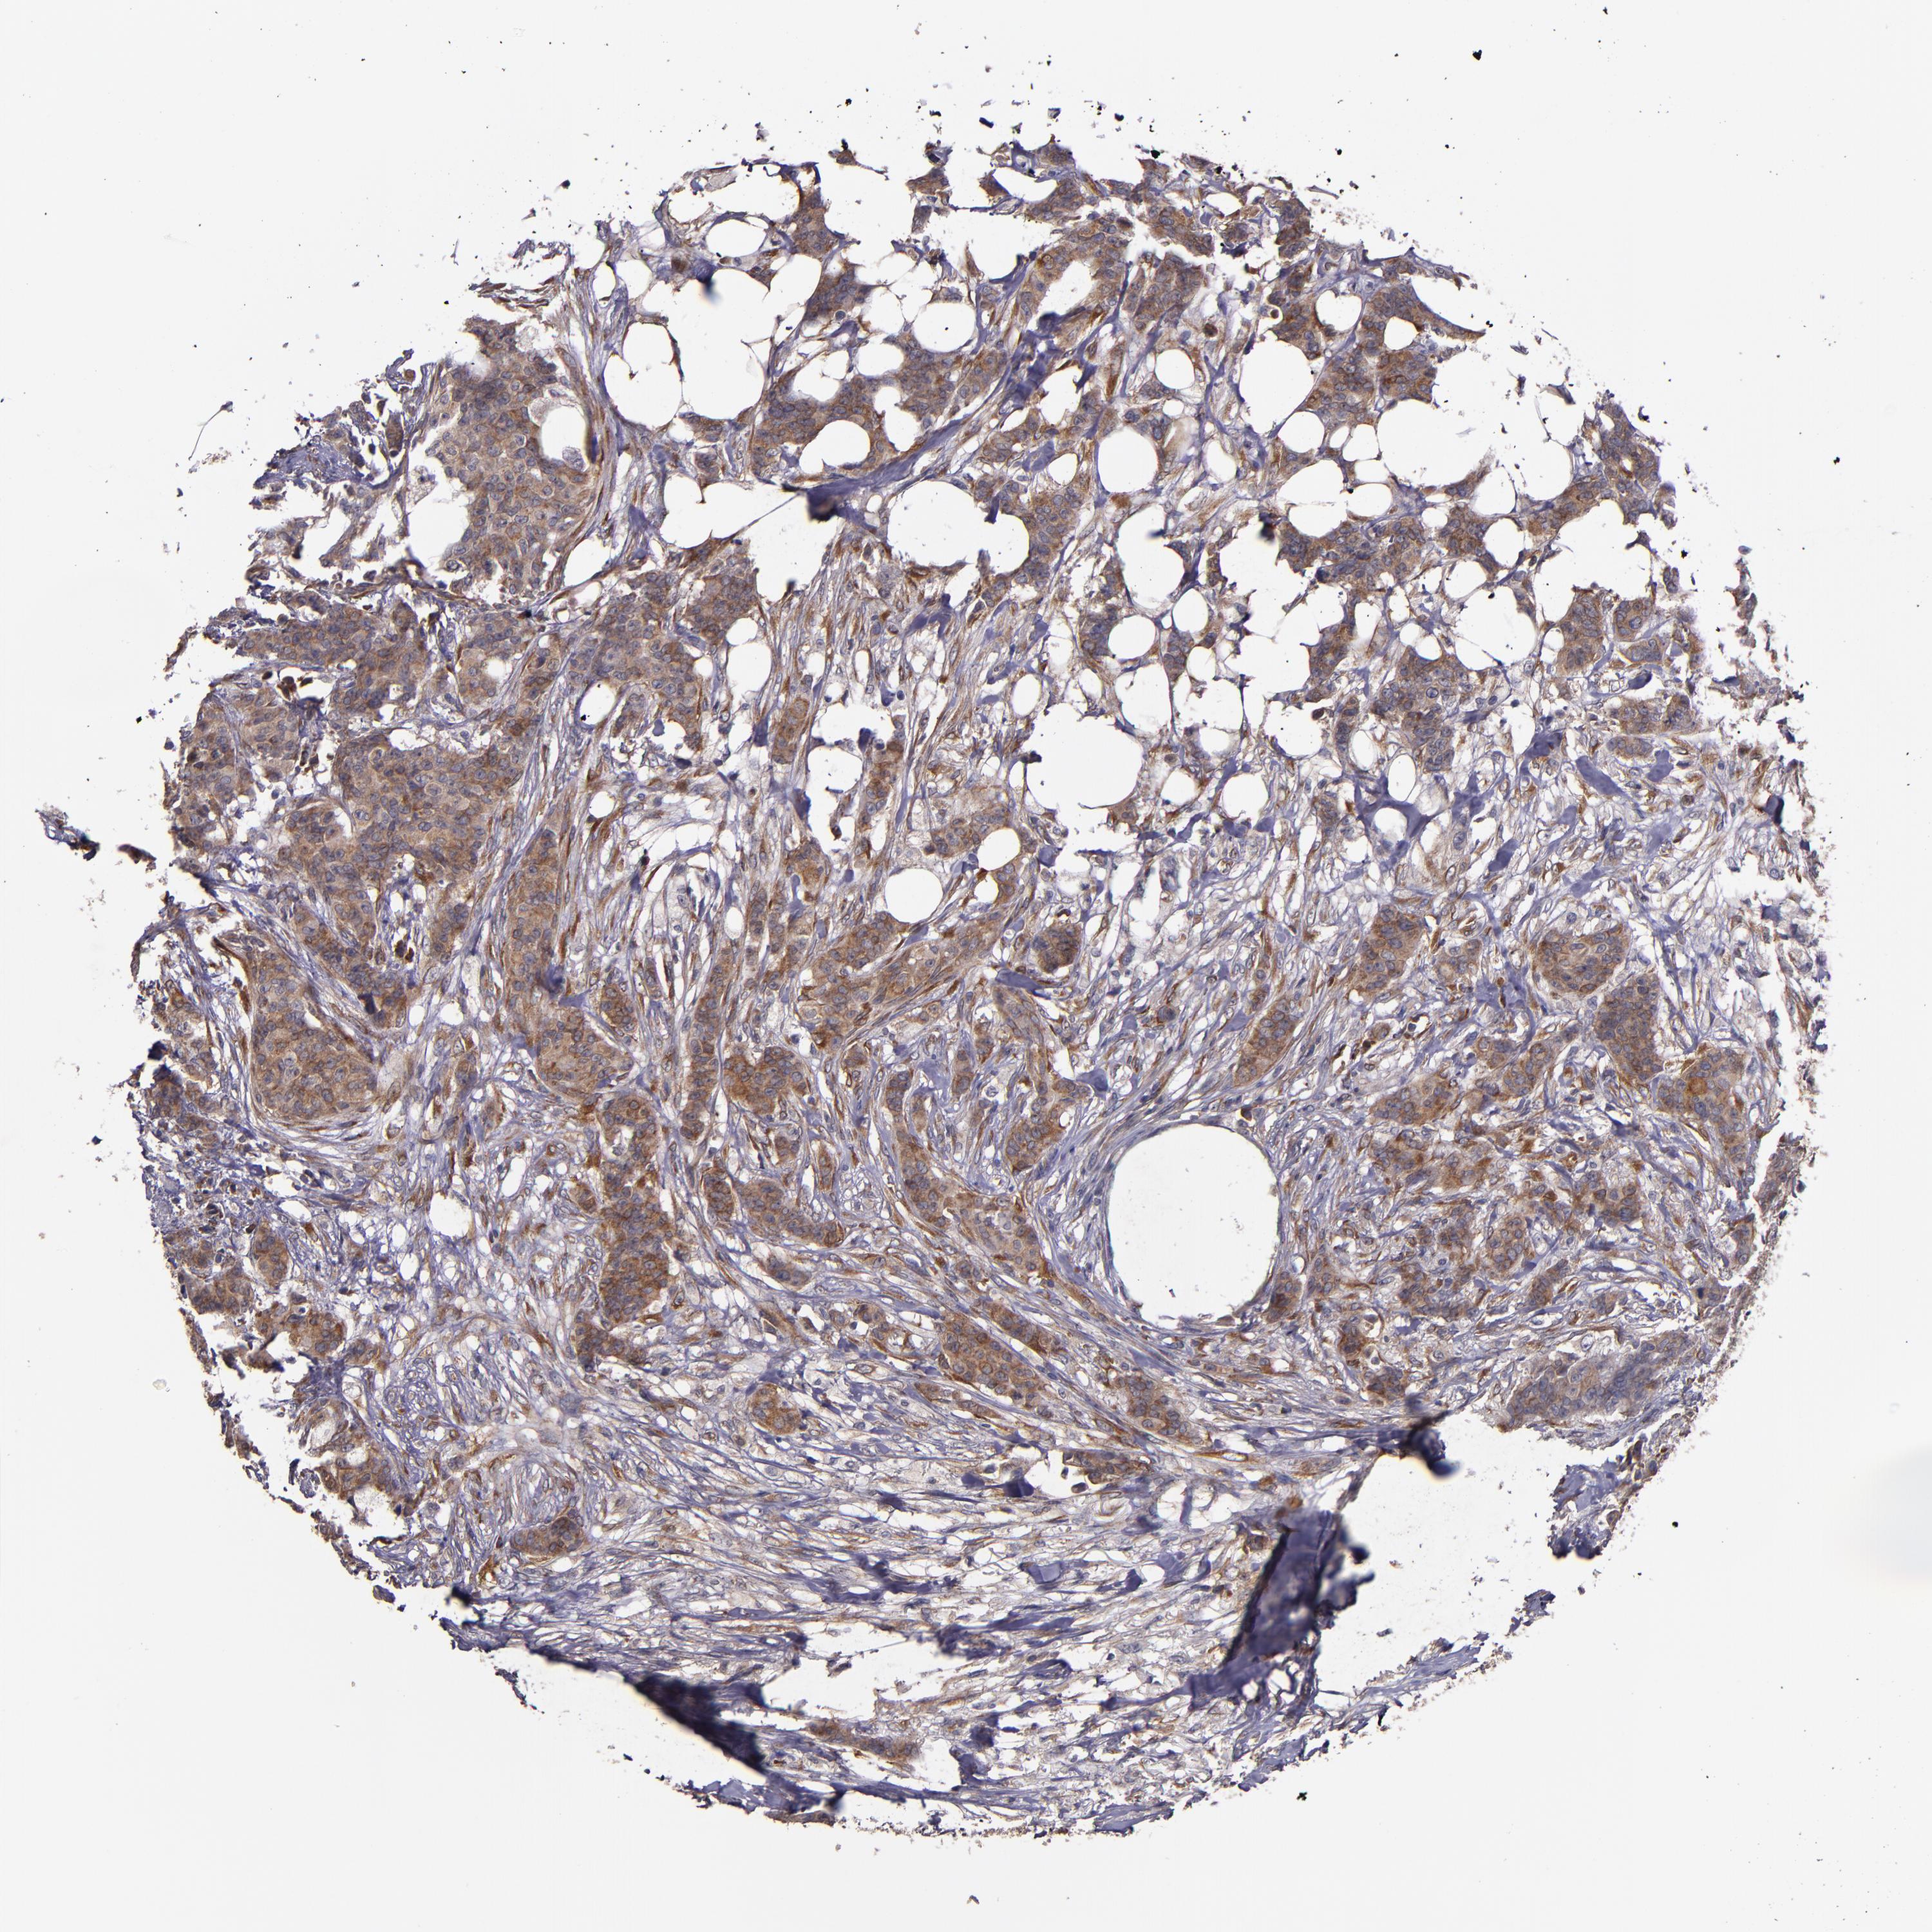

CANCER BREAST CANCER Show tissue menu

Breast cancer

Human cancer